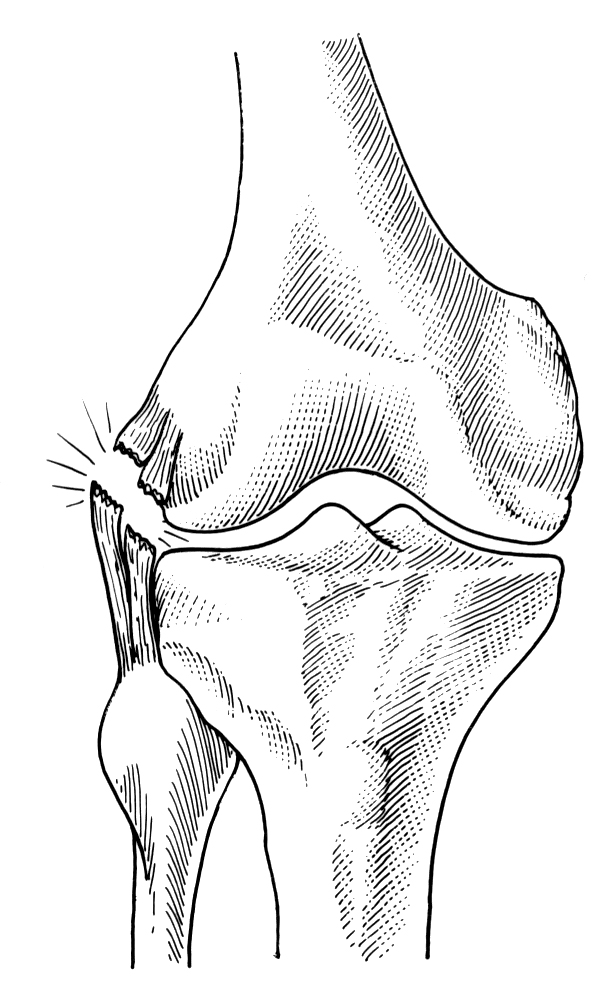

ISTORICUL ORTOPEDIEI SI TRAUMATOLOGIEI

ISTORICUL ORTOPEDIEI SI TRAUMATOLOGIEI - numele propus de Nicholas Andry - Egiptul antic - Citeste tot ... 800 cuvinte

Dimensiune mica

+ cu imagini |